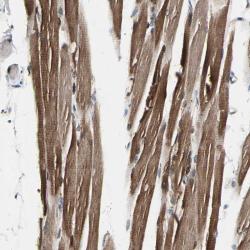

- Immunohistochemical staining of human skeletal muscle shows distinct cytoplasmic positivity in myocytes.

- Staining pattern partly consistent with experimental and/or bioinformatic data.